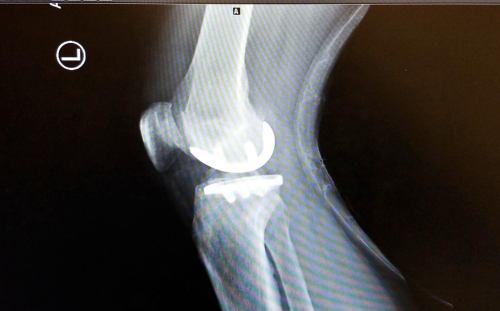

I scanned the x-rays onto my phone – here’s the best one. You can see how the top and bottom parts of the appliance are embedded in the bones and also the artificial padding that replaces my cartilage. When I spoke with Dr. Gott right after the surgery and asked him the state of my knee after he got into it, he said “Your knee was trashed. All the cartilage on that side was gone, all bone on bone.” The rest of the knee though was OK, hence only a partial replacement.

Anyway, pretty cool And the bowing of my left leg has been partially corrected – by the spacing increased between the two bones by the appliance. Science marches on. I’m now cleared to go to the gym for upper body work – lower body still with the physio – shower, and basically do anything as long as I don’t drive under the influence of pain meds. Nine days post op. I’m pleased. Dr. Gott , his staff, and White Plains Hospital – all excellent – 5 out of 5.